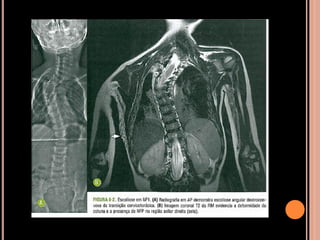

Escoliose:

 Ocorre em cerca de 10% dos pacientes

 Distróficas: remodelamento das vértebras,

alargamento do canal vertebral e dos forames

espinhosos; início precoce e rapidamente

progressiva;

 ou não distróficas = escoliose idiopática

NF1

 Costelas em fita;

 Múltiplas pseudoartroses: comprometimento da

tíbia é o mais comum;

 Hipoplasia dos elementos vertebrais posteriores;

 Remodelamento dos corpos vertebrais (10%);